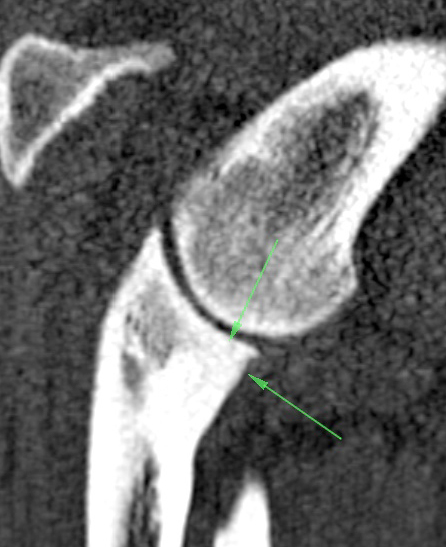

- This is some other still from the ct-scan with green arrows on it. I’ll try to explain in the next blog.